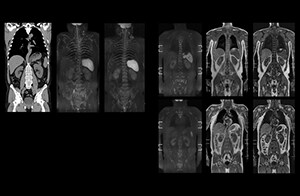

mDIXON FFE enriches the whole body exam without scan time penalty

“mDIXON FFE allows us to quickly get information we need to assess the presence of fat. That gives us more information when we need to diagnose bone lesions, and when we are asked to judge fat-containing lesions such as hepatocellular or renal carcinoma,” Dr. Nobusawa says. “The mDIXON fat images can help us to differentiate fatty bone marrow from bone lesions. This is especially useful in elderly people, who tend to have fattier bone marrow. The water images provide a high signal-to-noise ratio in the intestinal canal, which is valuable for visualizing lesions in the colon,” he says.

Kawasaki Sawai Hospital’s whole body protocol also includes an mDIXON FFE sequence. Because mDIXON provides images for four contrast types – water only, fat only, in-phase and out-of-phase – from a single acquisition, it is useful in many ways.

“In-phase and out-phase sagittal T1-weighted FFE images help us to visualize and further characterize bone lesions such as metastasis and bone-marrow hyperplasia that have high signal on DWI. These images are also used throughout radiotherapy, to monitor changes in the fatty bone marrow.”